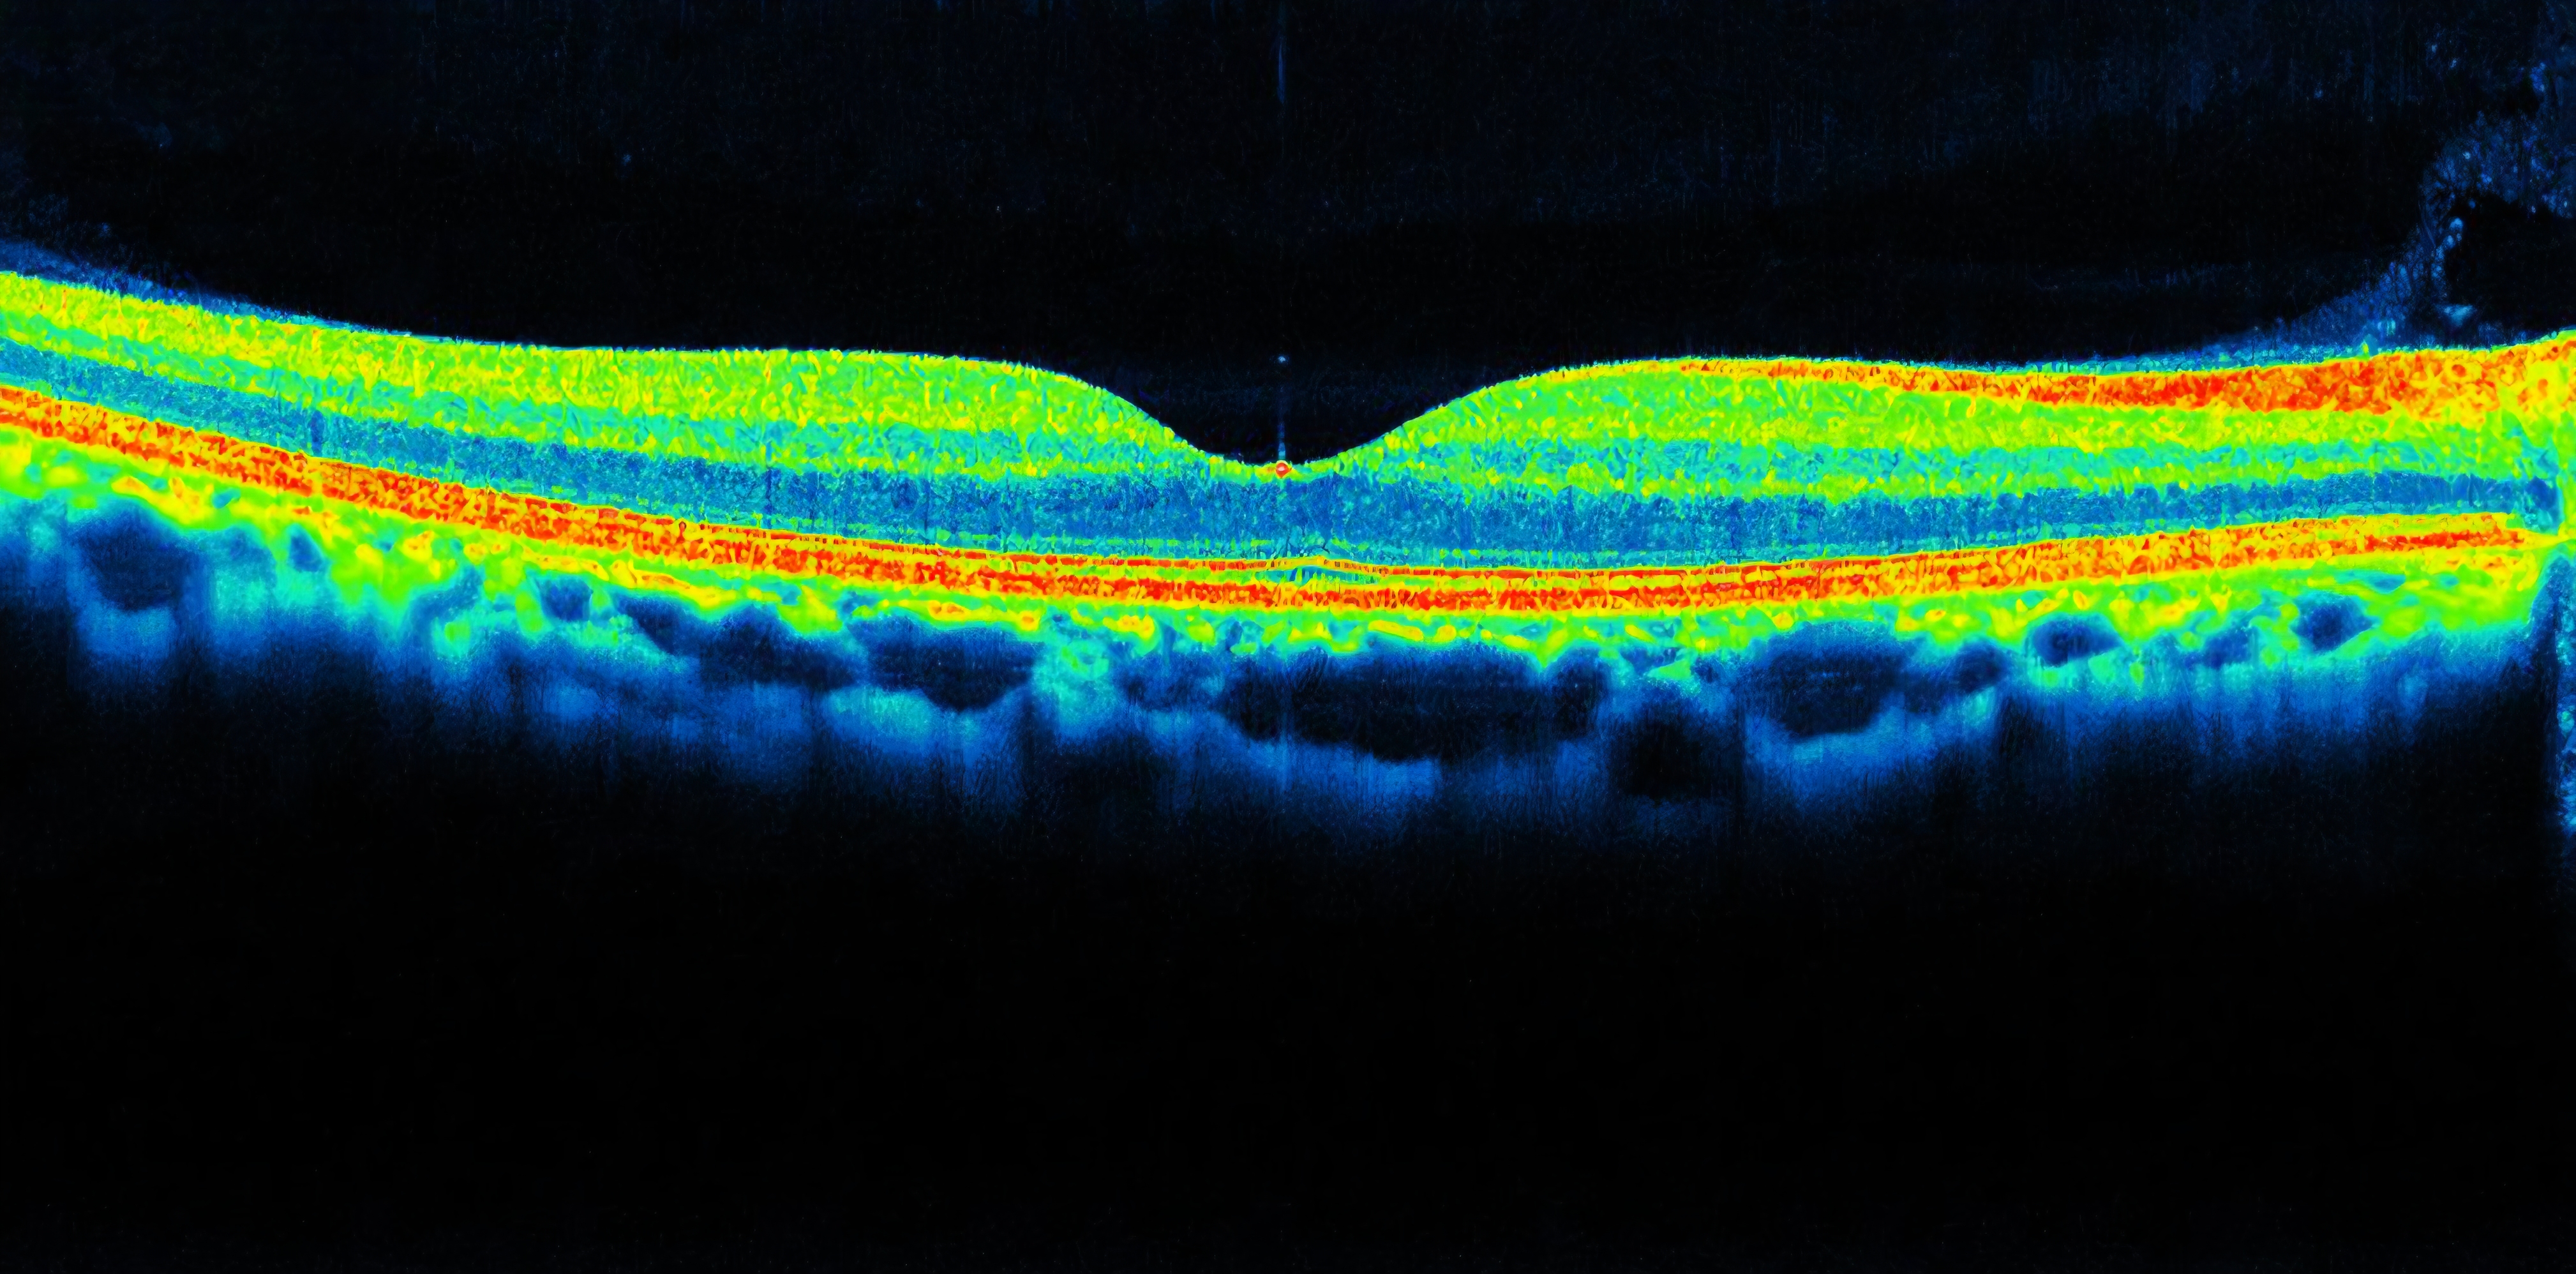

OCT Scanning

At R. A. Glass, we are passionate about eye health. As part of our commitment to provide you with the very highest standard of eye care, we have invested in cutting-edge Optical Coherence Tomography (OCT) technology which allows us to examine the back of your eyes in exceptional detail.